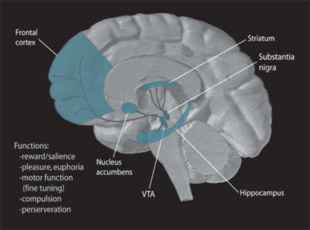

Dopamine

Dopamine is one of the more known neuromodulators involved in procedural memory. Evidence suggests that it may influence neural plasticity in memory systems by adapting brain processing when the environment is changing and an individual is then forced to make a behavioural choice or series of rapid decisions. It is very important in the process of "adaptive navigation", which serves to help different brain areas respond together during a new situation that has many unknown stimuli and features.[44] Dopamine pathways are dispersed all over the brain and this allows for parallel processing in many structures all at the same time. Currently most research points to the mesocorticolimbic dopamine pathway as the system most related to reward learning and psychological conditioning.[45]